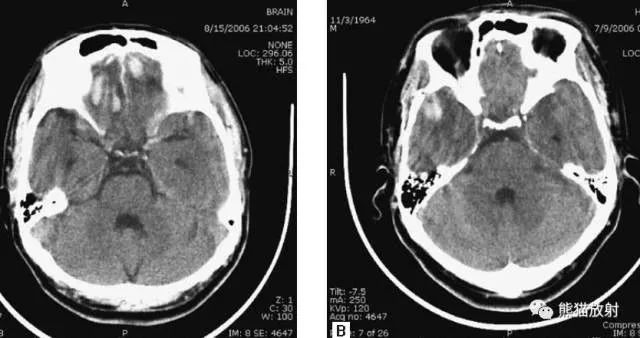

5、高血压性脑出血

高血压性脑出血:自发性出血;

继发于长期高血压及慢性血管病;

常见于基底节区、丘脑、脑桥、小脑。

A:占位效应,相邻脑沟、脑池消失;

F:脑出血破入四脑室。

▲钩回疝:

是当代偿机制不能适应占位性病变时的结果。

基底节区大量高血压性脑出血,破入脑室及蛛网膜下腔,周围水肿,脑干周围空间消失;脑干出血、脑积水。